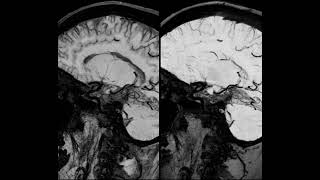

Direct vessel wall imaging (VWI) from dark blood MRI dataset video

Direct vessel wall imaging (VWI) from dark-blood MRI dataset

Direct vessel wall imaging (VWI) from dark-blood MRI dataset Vessel wall imaging using high resolution 3D CUBE T1 fat sat with MSDE and HyperSense

Direct vessel wall imaging (VWI) from dark-blood MRI dataset

Direct vessel wall imaging (VWI) from dark-blood MRI dataset Vessel wall imaging using high resolution 3D CUBE T1 fat sat with MSDE and HyperSense